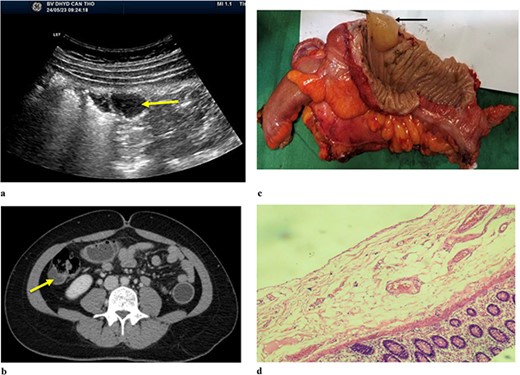

A 34-year-old female patient presented to the hospital due to a one-year history of right lower quadrant (RLQ) pain. There were no reported symptoms of weight loss or changes in bowel habits. She had no relevant medical or surgical history, and no family members had a history of gastrointestinal cancer. Physical examination revealed mild tenderness in the RLQ but was otherwise unremarkable. Abdominal ultrasound (Fig. 2) showed the right lumbar cystic lesion, adjacent to the ascending colon, the lesion appeared as a non-adhesive, anechoic structure with septations and no Doppler pattern. The size was ~35 × 17 × 26 mm. CT scan (Fig. 2b) demonstrated a cystic structure protruding into the lumen of the ascending colon, clearly margin, enhancing wall with a size was ~24 × 15 mm. A subsequent colonoscopy did not detect lesions. Based on the clinical and radiographic findings, she was diagnosed with a symptomatic colonic duplication cyst. Intraoperatively, an ascending paracolic cyst was found. The patient underwent laparoscopic right hemicolectomy, and she made an uneventful recovery and was discharged on the seventh day after the operation.

(a) Abdominal ulstrasound shows an arrow pointing to anechoic structure with septation. (b) Axial CT scan showing an arrow pointing to a cystic structure protruding into the lumen of ascending colon. (c) Arrow pointing to colonic duplication cyst. (d) Microscopic examination, the inner lining of the cyst consisted of flat epithelium containing mucin.

The macroscopic examination of the histopathology sample (Fig. 2c) identified a 20 mm cystic mass located adjacent to the ascending colon. Upon microscopic examination (Fig. 2d), it was observed that the inner lining of the cyst consisted of flat epithelium containing mucin.